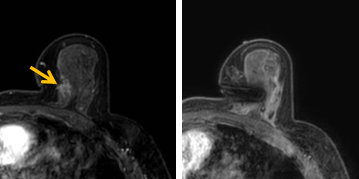

患者李女士磁共振檢查發(fā)現(xiàn)右乳內(nèi)側(cè)高度可疑病變,病變小摸不到,超聲和X線攝影(鉬靶)都看不到,怎么辦?要想明確病變性質(zhì),必須進(jìn)行磁共振引導(dǎo)下精準(zhǔn)足量的活檢,但是這種技術(shù)操作難度大、軟硬件要求高。

經(jīng)過仔細(xì)查體并分析所有影像資料,陳寶瑩發(fā)現(xiàn),病變靠近胸大肌,容易造成術(shù)中損傷。患者乳房較小,病變在內(nèi)側(cè),導(dǎo)致乳房不易固定,進(jìn)針難度大,與患者充分溝通后,陳寶瑩帶領(lǐng)團(tuán)隊,制定了細(xì)致的操作方案,術(shù)中,醫(yī)護(hù)團(tuán)隊反復(fù)調(diào)整體位和固定架的角度及方向,利用隔離技術(shù)保護(hù)好周圍組織。受乳房形態(tài)和病變位置的限制,醫(yī)生只能蹲著、跪著進(jìn)行操作,經(jīng)過30多分鐘終于順利完成,精準(zhǔn)獲取了足量的組織,而且一針到位,創(chuàng)傷小、出血少,患者沒有任何不適,做完即回家休息。幾天后,病理證實是一種特殊類型的早期乳腺癌,為后續(xù)進(jìn)一步治療方案的制訂提供了準(zhǔn)確依據(jù)。